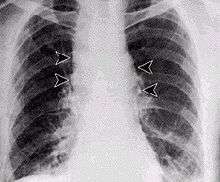

Inhalational anthrax, mediastinal widening

Anthrax can enter the human body through the intestines (ingestion), lungs (inhalation), or skin (cutaneous) and causes distinct clinical symptoms based on its site of entry. In general, an infected human will be quarantined. However, anthrax does not usually spread from an infected human to a noninfected human. But, if the disease is fatal to the person's body, its mass of anthrax bacilli becomes a potential source of infection to others and special precautions should be used to prevent further contamination. Inhalational anthrax, if left untreated until obvious symptoms occur, may be fatal.